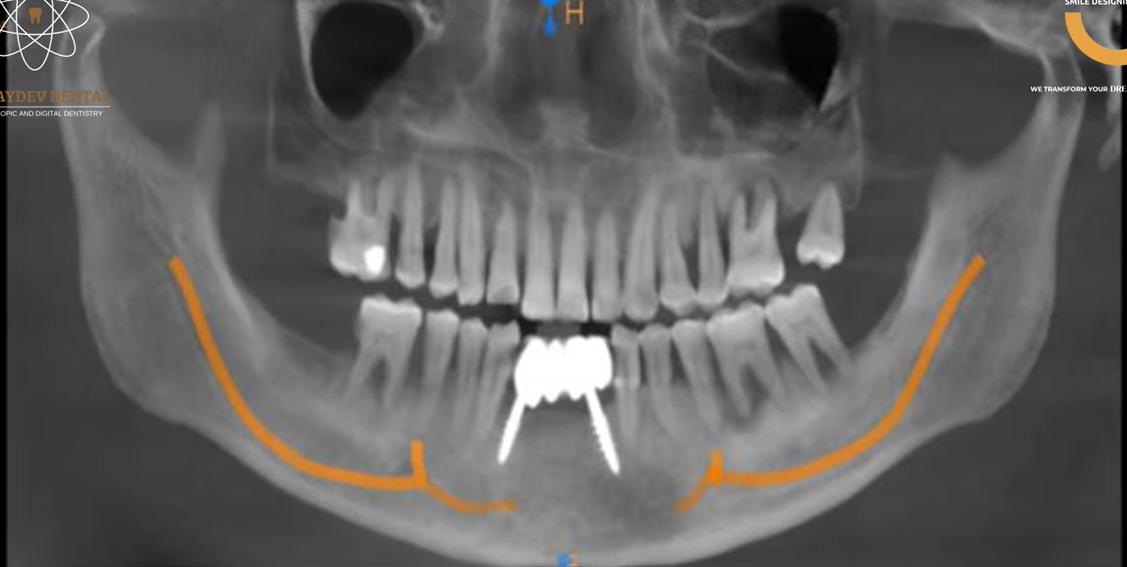

- The patient underwent comprehensive 3D digital scans, which were used to create a precise 3D digital guide for the surgery.

- Digital Smile Design (DSD) was employed to plan the optimal placement of the implants and ensure proper alignment.

- Full-mouth dental implant surgery was executed with precision on the day of the surgery, following the prepared digital guide.

- The surgery aimed to restore function and aesthetics by placing implants that would support a full set of teeth for the patient.